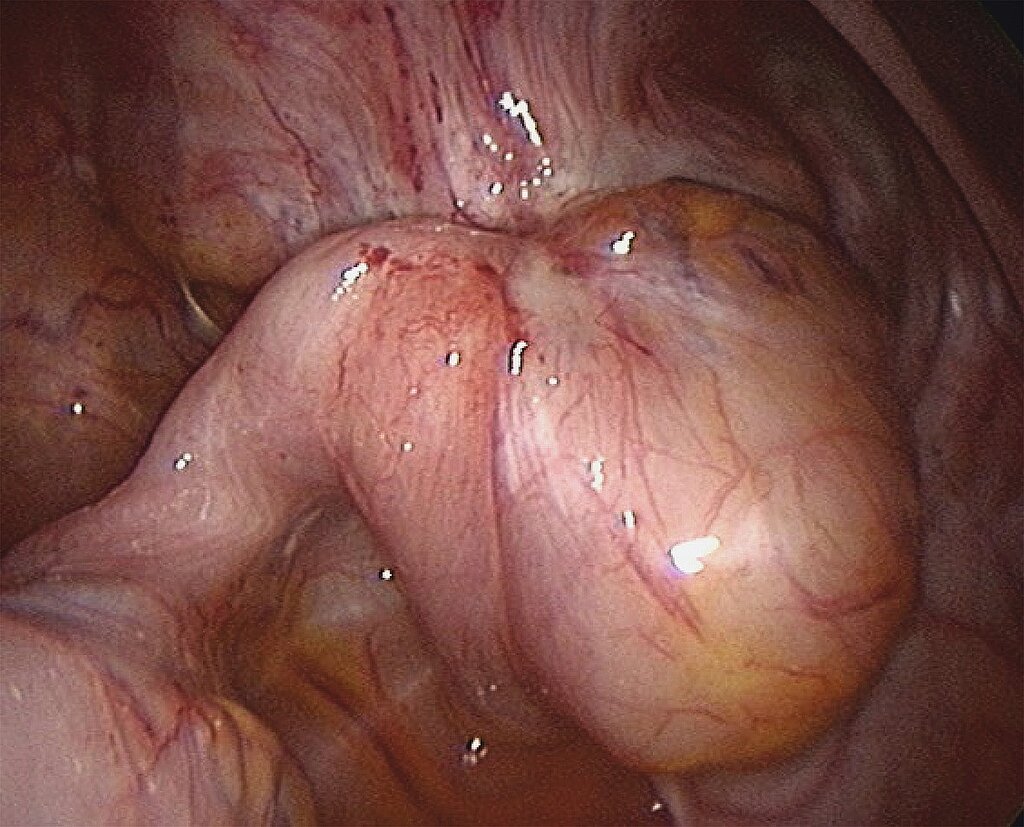

Peritoneale Endometriose

Diese häufigste Form der Endometriose tritt im gesamten Bauchraum und in unterschiedlicher Ausprägung und Form auf, oft auch in Kombination mit der ovariellen und der TIE (Abb. 9). In aller Regel lassen sich die Herde gut mit der Schere abtragen oder durch Koagulation zerstören. Dabei können mikroskopisch kleine Herde dem Operateur verborgen bleiben und somit ein Rezidiv vorprogrammieren.